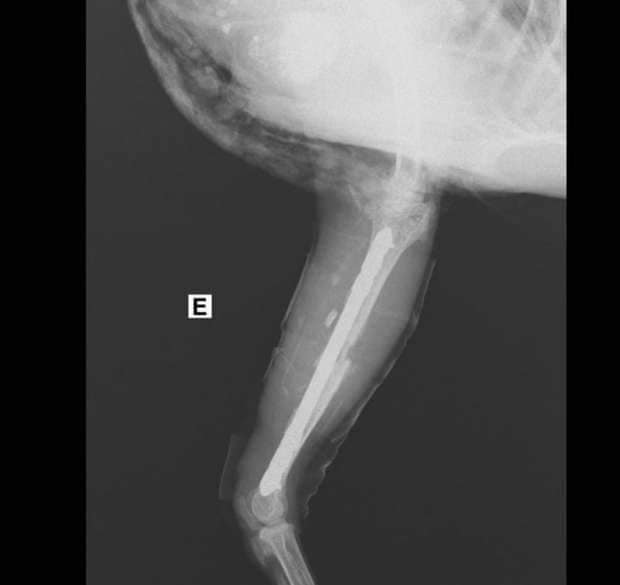

وكان طبيبان بيطريان قد أجريا عملية جراحية لـ"فرخة" بها كسر وتم تركيب شرائح ومسامير طبية لها ويطلق عليها اسم "ليكسي" ووضعت تحت الملاحظة، وتم وضعها على أجهزة وتركيب محاليل لها كبديل عن الطعام. (سبوتنيك)